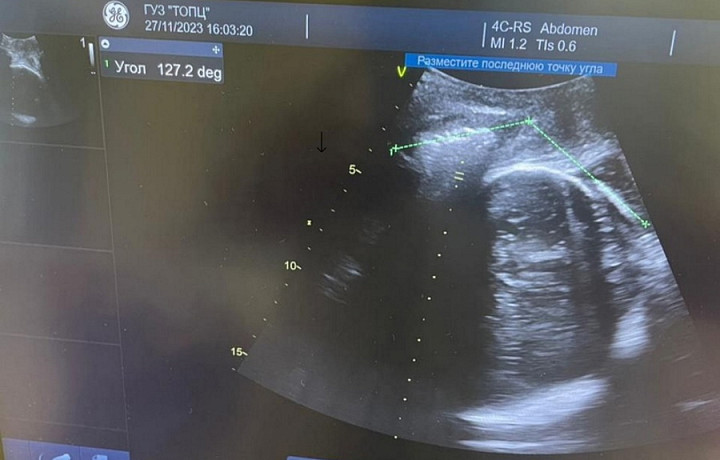

Тульский областной перинатальный центр внедряет новый метод ведения родов в новом корпусе. Речь идет об ультразвуковой диагностике течения родов, сообщает пресс-служба медучреждения.

Этот способ дает возможность в режиме реального времени точно определять положение головки плода и ее продвижение в потужном периоде родов. Так можно выбрать возможный метод родоразрешения: кесарево сечение или естественные роды.

«Нами уже проведено более 20 родов с использованием ультразвуковой диагностики. Применение этого метода во время родов позволяет нам с одной стороны своевременно решать вопрос об оперативном родоразрешении, с другой стороны — избежать лишних оперативных вмешательств. Другим немаловажным аспектом является удовлетворенность рожениц. Женщины видят продвижение головки в родах и это позволяет им достичь психологического комфорта и спокойствия», – пояснил заместитель главного врача по акушерству и гинекологии, кандидат медицинских наук Петр Мартыненко.